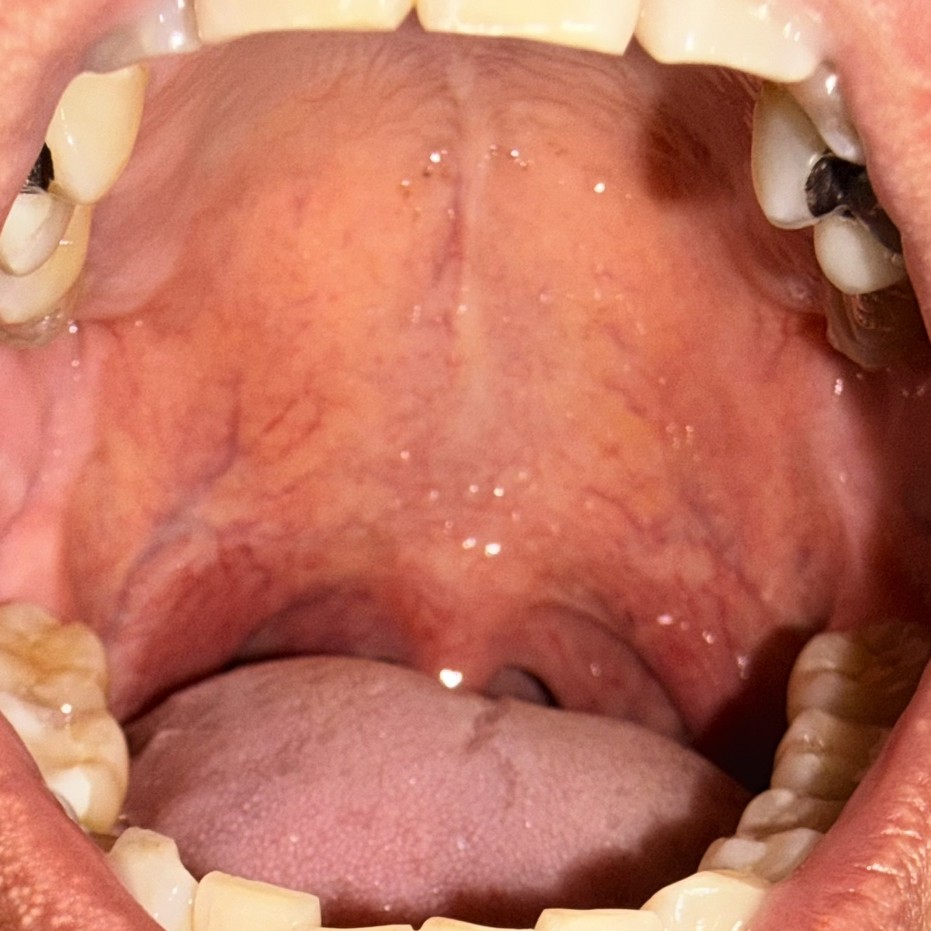

症例2 施術後1カ月経過